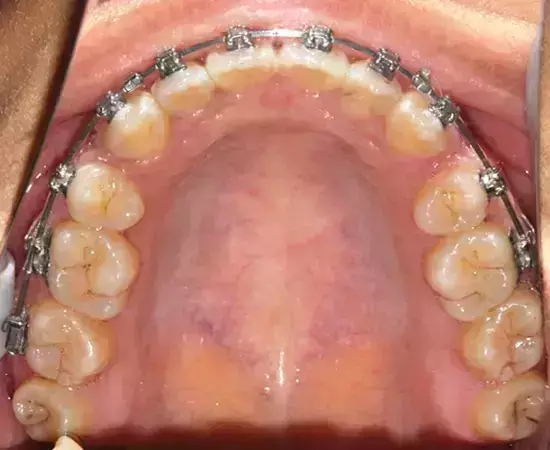

Damon 病例分享:安氏 II 類(lèi)二分類(lèi)露齦笑的矯治(董一磊)

治療前后對(duì)比